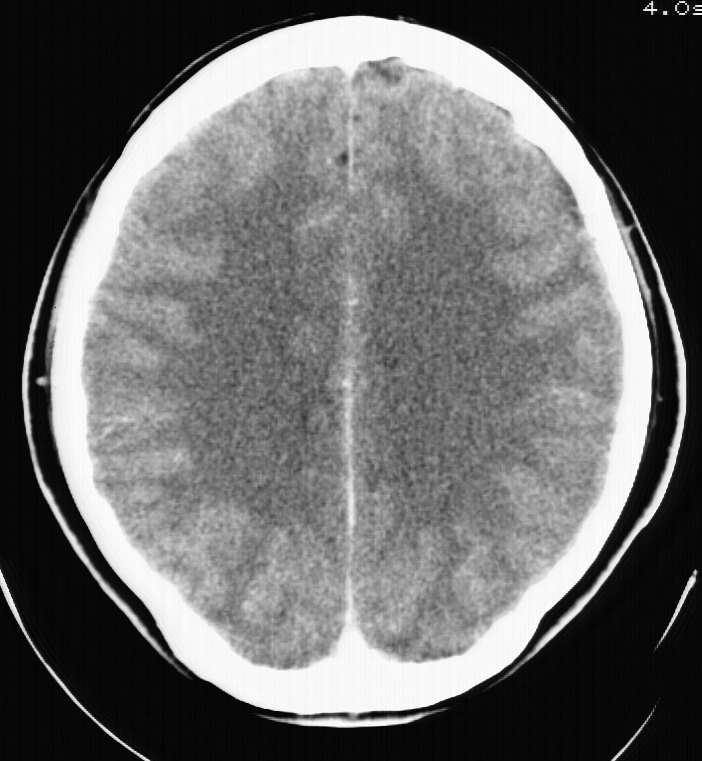

标题: CT5853:右额叶上部占位请会诊

女,34岁,自述头晕胀2年,近期感精神恍惚,无发热,实验室检查阴性。

右顶叶靠近脑表面圆形低密度灶,周围无水肿及占位效应,增强病灶无明显强化,考虑:右顶叶低分级星型细胞瘤。

右额叶上部皮质区见类圆形低密度区,边界不清,无强化,无钙化。

支持大多数战友的意见,1级星形细胞瘤。